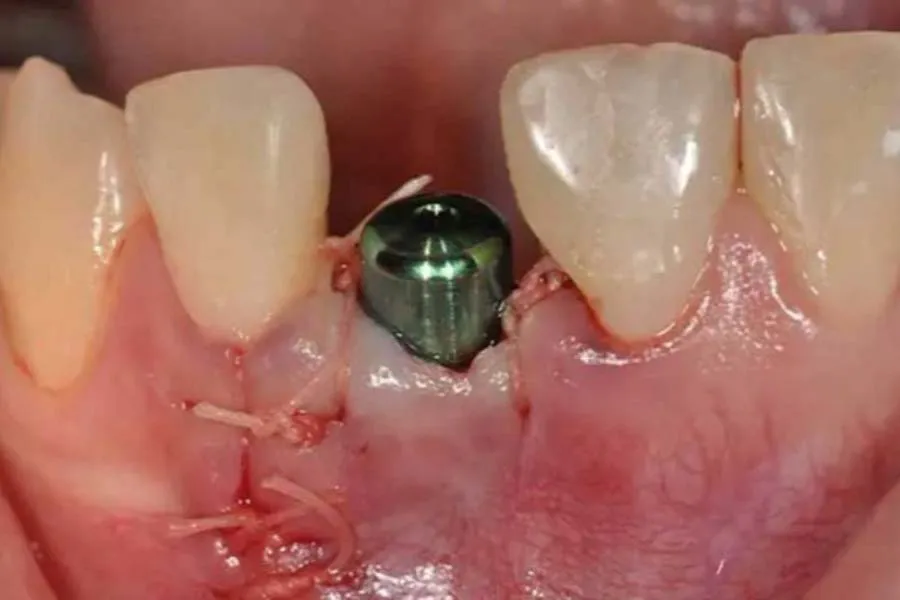

- مشاهده فیزیکی: دیدن لبههای باز لثه که استخوان یا پایه ایمپلنت (هیلینگ) از میان آن پیداست.

اگر لبههای زخم از هم دور نشده باشند و خونریزی نداشته باشید، افتادن یک تکه نخ معمولاً خطرناک نیست. خطر اصلی زمانی است که ایمپلنت یا استخوان پیوند زده شده به طور کامل در معرض محیط دهان قرار بگیرد.

بررسی نوع بخیه

بدانید که بخیه ایمپلنت بعد از چند روز جذب میشود. معمولاً این فرآیند از روز پنجم شروع شده و تا دو هفته کامل میشود. اگر در روزهای اول (۱ تا ۳) بخیه باز شود، نیاز به مداخله جراح است. اما در روزهای پایانی، احتمالاً بخشی از فرآیند طبیعی ترمیم است.

آیا راهی برای ایمپلنت بدون بخیه وجود دارد؟

بله، در روشهای دیجیتال و پانچ (Flapless)، جراحی به قدری دقیق و با برش حداقل انجام میشود که گاهی نیاز به هیچ بخیهای نیست یا فقط یک بخیه نمادین زده میشود. برای مثال، بسیاری از بیماران به دنبال جراحی ایمپلنت با بخیه جذبی هستند تا ریسکهای مربوط به کشیدن بخیه و تحریکات ناشی از آن را به حداقل برسانند که توصیه میکنیم مطلب جامع و کامل انواع مراقبتها و روشهای جراحی ایمپلنت با بخیه جذبی در اصفهان از سایت دکتر حسن مومنی متخصص جراح دهان ، فک و صورت را مطالعه فرمایید.